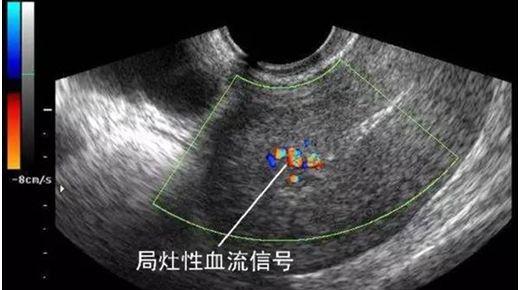

子宫内膜不均是超声回声的一种描述,通常是由于内膜下的血管分布不均所导致的,对于备孕的女士如果超声显示“子宫内膜回声不均”一定要行宫腔镜检查,并治疗病变,以保证良好的宫腔环境,从而提高妊娠率;对于年龄较大的女士则要宫腔镜结合病理,排除恶性病变。

正常的子宫内膜与雌孕激素周期及卵泡发育周期是同步的,并在一定程度上反映了内分泌水平的变化,无论是何种原因导致的不孕或者反复自然流产,大部分表现在子宫内膜结构异常、炎症反应、雌孕激素减少等,影响子宫内膜厚度,形态,血流的变化,从而影响胚胎着床。在治疗过程中,需要定期检测子宫对内膜血液灌注,正确指导用药及治疗,提高妊娠率及保胎成功率。

超声是妇产科的主要辅助检查手段,某些疾病的早期,在超声表现不典型,不可能替代病理,遇到超声提示:内膜回声不均时应该警惕以上情况的出现,可以诊断性刮宫送病理结 合宫腔镜检查还要结合临床及其他检查,进一步明确诊断。同时不要紧张,因为有一部分是正常的,如:药物流产后,子宫内膜没有来得及修复,这种情况是正常的,也可见于使⽤外源性雌激素药物等。